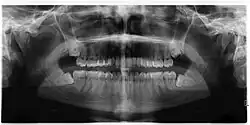

If the tooth cannot be assessed with clinical exam alone, the diagnosis is made using either a panoramic radiograph or cone-beam CT. Where unerupted wisdom teeth still have eruption potential several predictors are used to determine the chance of the teeth becoming impacted. The ratio of space between the tooth crown length and the amount of space available, the angle of the teeth compared to the other teeth are the two most commonly used predictors, with the space ratio being the most accurate. Despite the capacity for movement into early adulthood, the likelihood that the tooth will become impacted can be predicted when the ratio of space available to the length of the crown of the tooth is under 1.[5]: 141